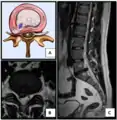

Click images to see larger versions

• Magnetic resonance imaging is the gold standard study for confirming a suspected LDH. With a diagnostic accuracy of 97%, it is the most sensitive study to visualize a herniated disc due to its significant ability in soft tissue visualization. MRI also has higher inter-observer reliability than other imaging modalities. It suggests disc herniation when it shows an increased T2-weighted signal at the posterior 10% of the disc. Degenerative disc diseases have shown a correlation with Modic type 1 changes. When evaluating for postoperative lumbar radiculopathies, the recommendation is that the MRI is performed with contrast unless otherwise contraindicated. MRI is more effective than CT in distinguishing inflammatory, malignant, or inflammatory etiologies of LDH. It is indicated relatively early in the course of evaluation (<8 weeks) when the patient presents with relative indications like significant pain, neurological motor deficits, and cauda equina syndrome. Diffusion tensor imaging is a type of MRI sequence used for detecting microstructural changes in the nerve root. It may be beneficial in understanding the changes that occur after herniated lumbar disc compresses a nerve root, and might help in differentiating the patients that need surgical intervention. In patients with a high suspicion of radiculopathy due to lumbar disc herniation, yet the MRI is equivocal or negative, nerve conduction studies are indicated.[44] T2-weighted images allow for clear visualization of protruded disc material in the spinal canal.